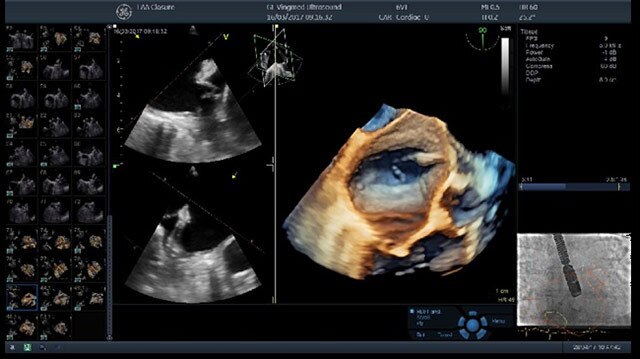

Ultra-high single-beat volume rates With TEE procedures growing, so is the need to find ways to achieve the benefits of 4D imaging without compromising productivity. VmaxTM enabled by cSound™ 2.0 offers ultra-high 4D volume rates acquired in single beat acquisition with no loss of image quality. Elimination of ECG gated multibeat/stitching acquisition provides enhanced overview of structures and function in cases with high and/or irregular heart rhythm - which potentially reduces interventional procedure time and improves patient outcomes.

4D TEE color imaging with Vmax